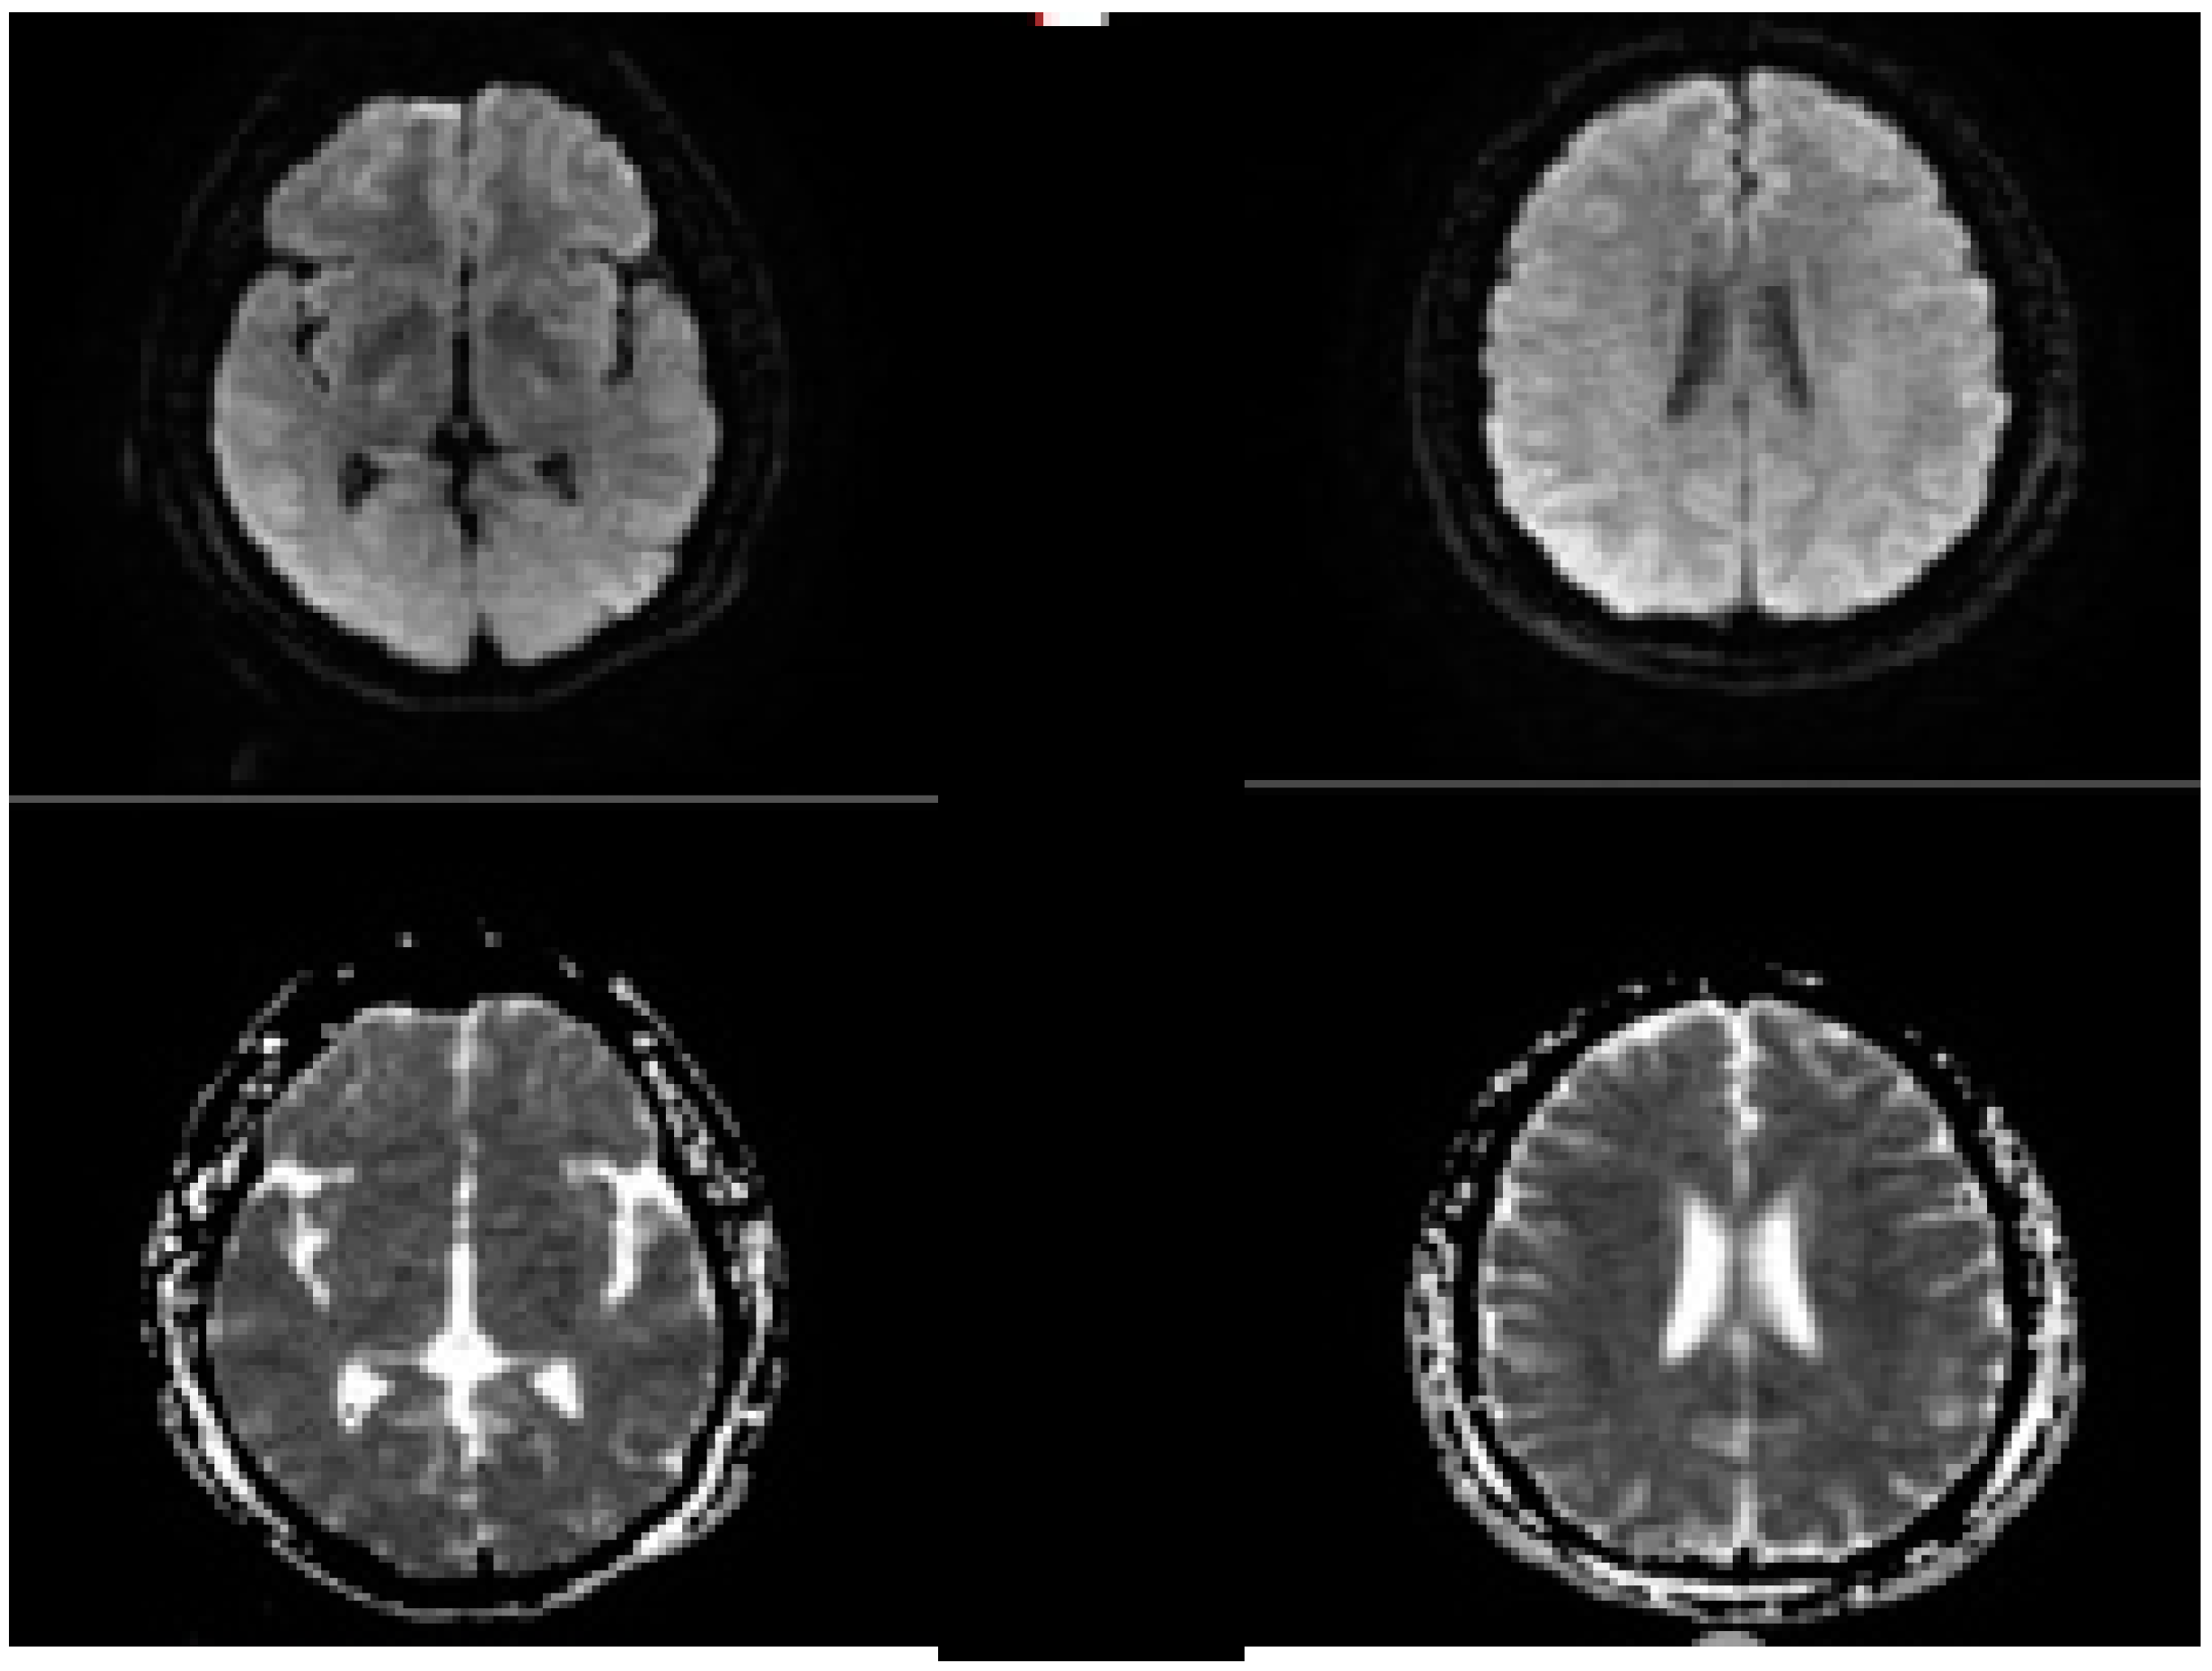

2.5. Evolution of the Concept of the Tissue Window and Late Window Trials